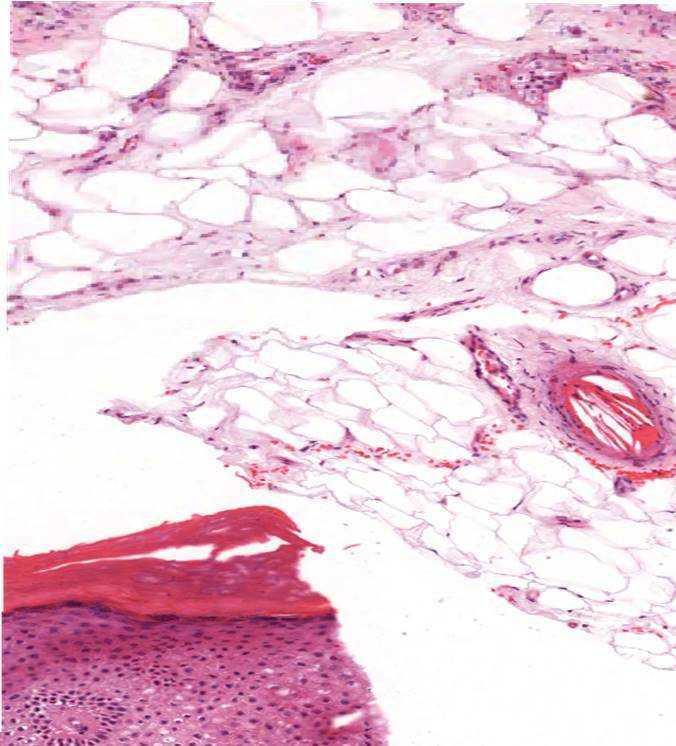

Durante la hospitalización mantiene buen estado general, niveles tensionales dentro de los parámetros normales con medicación hipotensora y diuresis conservada (1500-2000 ml/día). Ante la sospecha de enfermedad sistémica ateroembólica por colesterol, se inició desde el primer día tratamiento con metilprednisolona (0,3 mg/kg/día vía oral) y atorvastatina 80 mg, con suspensión del acenocumarol. Se interconsultó con oftalmología para la exploración del fondo de ojo en busca de las placas de Hollenhorst, siendo este normal. El índice tobillo-brazo también resultó normal. El ecocardiograma no mostró masas intracardíacas ni otros datos de interés, aunque durante su realización se observaron rachas de fibrilación auricular autolimitadas. Se llevó a cabo una biopsia cutánea que fue compatible y concluyente para el diagnóstico de ateroembolia por cristales de colesterol (figura 2). La función renal se mantuvo estable respecto a los valores previos al menos durante 7-10 días, con progresivo descenso posterior, siendo la creatinina al alta de 3,3 mg/dl. Tras el inicio del tratamiento con esteroides, las lesiones violáceas en ambas piernas fueron desapareciendo. Al alta se mantuvo el tratamiento con esteroides en igual dosis para iniciar pauta de descenso al mes, coincidiendo con la revisión en la consulta de nefrología. Se solicitó valoración por cardiología y, por tratarse de un paciente con un riesgo cardioembólico elevado con una puntuación en la escala de riesgo CHADS2 de 4, se indicó tratamiento anticoagulante con heparina de bajo peso molecular (HBPM). En la revisión ya no presentaba lesiones cutáneas, la creatinina sérica era de 2,8 mg/dl y aún mantiene tratamiento con HBPM. En la figura 3 se puede ver la evolución de la creatinina sérica desde la introducción del acenocumarol y la mejoría posterior tras el inicio del tratamiento con corticoides.

La biopsia del órgano afectado confirma el diagnóstico de la enfermedad. El patrón de oro es la piel, cuya importancia radica en la accesibilidad, fácil realización y baja mortalidad, además del alto rendimiento de hasta un 92 %5. En la histopatología es patognomónica la visualización dentro de los vasos de la unión dermohipodérmica de hendiduras alargadas biconvexas en forma de agujas5. En nuestro caso clínico el antecedente farmacológico y las manifestaciones clínicas eran muy sugestivos de la ateroembolia por colesterol, pero la biopsia cutánea fue determinante para el diagnóstico final.

Figura 2. A nivel de panículo adiposo se evidencian vasos ocluidos por material fibrinoso con espacios claros de ángulos sugestivos de cristales de colesterol.